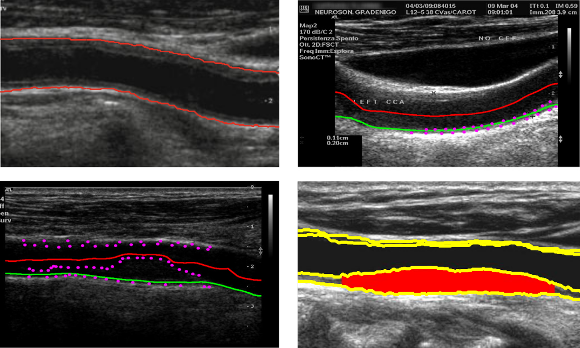

O projeto Carotid CAD tem como objetivo medir marcadores macrovasculares da aterosclerose, tais como a espessura da camada íntima-média e a dimensão de estenose em imagens de ultrassons da carótida. Este projeto estuda a relação destes marcadores com a presença de doenças nos vasos cerebrais.

A ultrassonografia da artéria carótida comum (ACC) tornou-se uma técnica amplamente usada para diagnosticar a aterosclerose e doenças associadas, uma vez que se trata de uma tecnologia de imagiologia médica de alta resolução não invasiva, de baixo custo. A partir de uma imagem longitudinal ultrassom da ACC, é possível medir a espessura da camada íntima-média, o diâmetro do lúmen, e a dimensão de estenose.

A medição de marcadores macrovasculares relacionada com a espessura da camada íntima-média, grau de estenose, aglomeração ou morfologia da placa a partir de imagens ultrassom da carótida pode ser usada para obter um diagnóstico precoce da aterosclerose e avaliar o risco de AVC.

O principal objetivo do Laboratório de Imagem Médica consiste em conceber e implementar metodologias por forma a obter automaticamente estes marcadores e desenvolver ferramentas CAD que permitam aos médicos obter um diagnóstico precoce da condição do paciente.